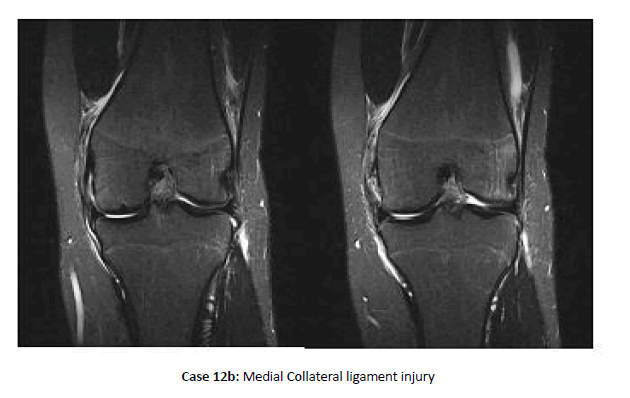

Case 12: Collateral ligaments injuries

Collateral ligaments injuries are shown in Cases 12a and 12b.

Note: Isolated collateral ligament injuries are rare in adolescent athletes. MCL injuries, one-quarter of which occurred in conjunction with patellar instability events, were 4 times more common than LCL injuries, one quarter of which have other posterolateral corner structures involved. Grade III injuries represent 20% to 25% of collateral ligament injuries and occurred most in football and soccer.